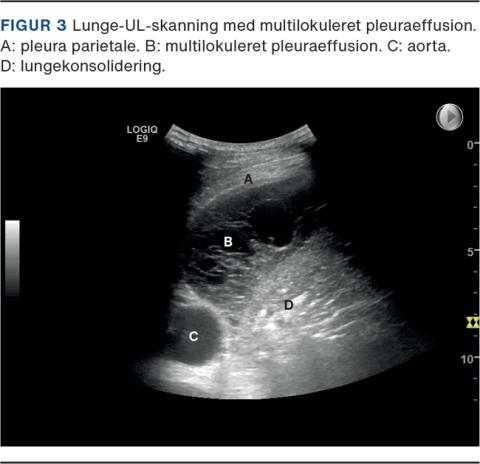

Hos patienter med multilokuleret pleuraeffusion, dvs. mange lommedannelser pga. intrapleurale septae (Figur 3), kan udtømning af pleuravæske være en udfordring. Hos udvalgte patienter kan intrapleural behandling med fibrinolyse (alteplase) og DNAse (dornase alfa) indgivet gennem IPC eller vanligt pleuradræn anvendes til opløsning af septae [23, 24]. Denne behandling bør varetages på specialiserede lungemedicinske afdelinger. Der gives typisk to behandlinger dagligt i tre dage, som ved empyem. Smerter og blødning er de alvorligste bivirkninger (hhv. ca. 12% og 4%) [23, 25]. Der er ikke evidens for, at fibrinolyse forud for pleurodese øger antallet af succesfulde pleurodeser [26].